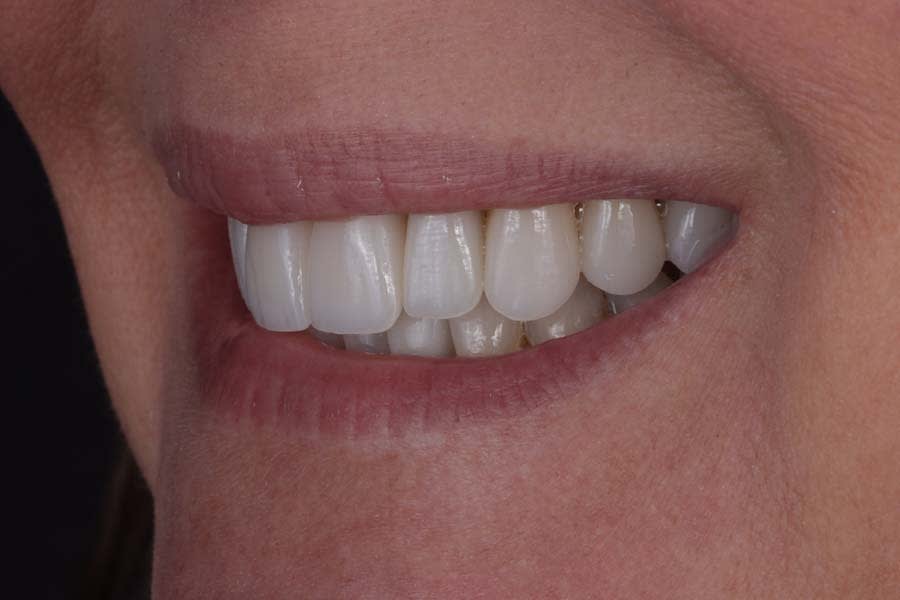

Post-treatment photographs demonstrating the successful outcome of the case are shown in Figure 15 through Figure 19.